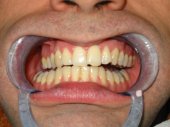

tratamiento, en la pérdida inevitable de los dientes afectados. Este proceso es consecuencia del llamado TRAUMA OCLUSAL en el que la falta de higiene (placa bacteriana) actúa como agravante. El TRAUMA OCLUSAL es la consecuencia de la pérdida del equilibrio oclusal masticatorio. El dr. Planas es quien mejor ha estudiado y comprendido el trauma oclusal, de tal manera que su conocimiento hace que el tratamiento de los procesos de afectación parodontal resulte efectivo. Eliminando el trauma oclusal cesa la inflamación y el sangrado gingival, se detiene la recesión gingival, desaparece la hipersensibilidad dentinaria, cesa la pérdida de hueso y la movilidad dentaria se reduce. Por todo ello consideramos que el tratamiento de la enfermedad periodontal debe encararse siempre desde el estudio y tratamiento del trauma oclusal, acompañado de los tratamientos necesarios para eliminar la placa bacteriana y el sarro depositado en el parodonto. En la animación se ve el efecto parodontal de una masticación unilateral; la pérdida de soporte óseo en los incisivos con su desplazamiento y apertura de espacios entre dientes. |

Alteraciones de los tejidos parodontales (encía, ligamento y hueso) por problemas funcionales |

Sangrado gingival espontáneo, infecciones

en las encías o movilidad dentaria debidos al desequilibrio oclusal